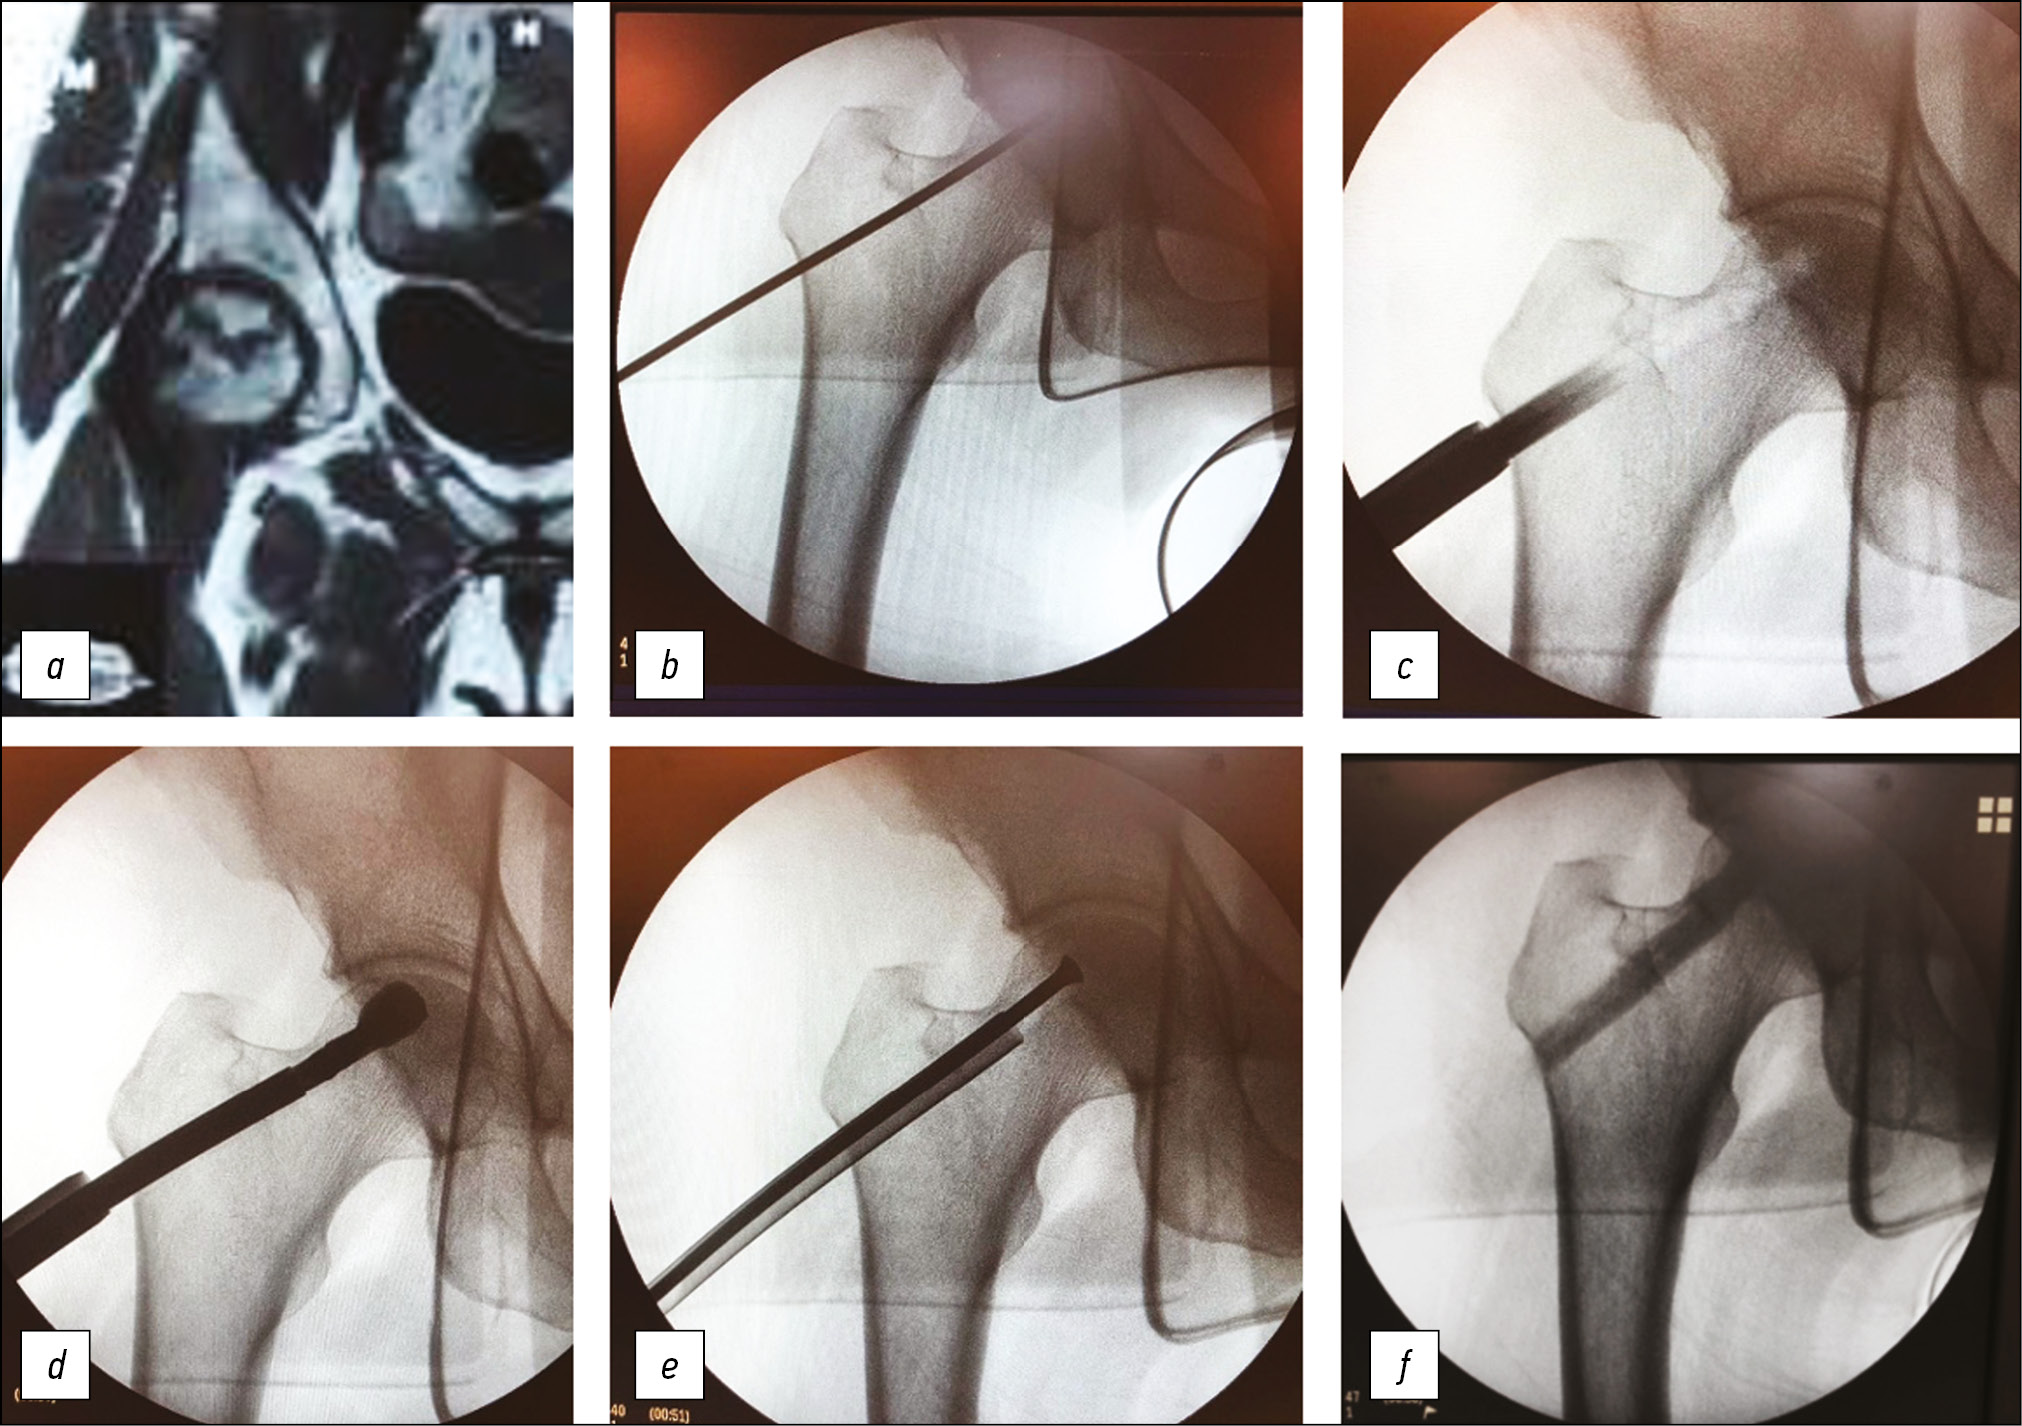

Ключевые этапы операции у пациентов группы 1 представлены на рис. 1.

Рис. 1. Этапы операции декомпрессии очага некроза с использованием чрескожного раздвижного лезвия с комбинированной пластикой костного дефекта. a — магнитно-резонансная томограмма аваскулярного некроза головки бедренной кости II стадии; b — установка направляющей спицы в центр зоны некроза (положение определяется в результате предоперационного планирования); c — рассверливание по спице; d — удаление некроза при помощи раздвижного лезвия; e — замещение дефекта в головке губчатой аутокостью; f — заполнение канала шейки бедренной кости жидким трансплантатом из сульфата кальция.

Доступ к зоне некроза и его парциальное удаление были осуществлены при помощи чрескожного раздвижного лезвия. Костная пластика в головке бедренной кости выполнялась при помощи губчатого аутотранс-плантата из проксимального отдела ипсилатеральной голени, канал шейки бедренной кости был заполнен жидким самозастывающим трансплантатом из сульфата кальция.